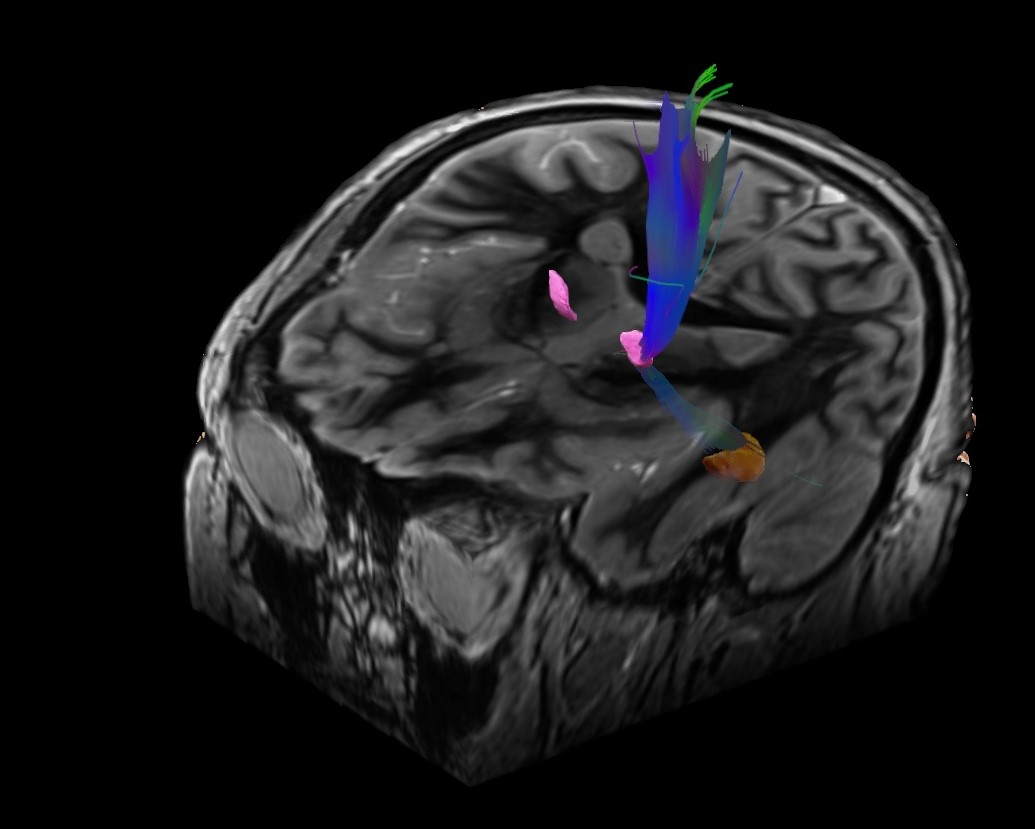

U Specijalnoj bolnici Radiochirurgia Zagreb u veljači 2024. na uređaju Cyberknife S7 uz programsku podršku Brainlab Elements napravljena je prva radiokirurška talamotomija u 72- godišnje bolesnice s esencijalnim tremorom. Ovo je prvi takav postupak u široj regiji gdje se koristi submilimetarska preciznost i robotsko navođenje u isporuci velike doze fokusiranog zračenja bez upotrebe invazivnih metoda imobilizacije. Cilj ovog liječenja je ablacija VIM jezgre talamusa. Postupak je bezbolan, provodi se jednokratno i traje oko 30-40 minuta. Za uspješno liječenje neophodan je dobar timski rad i suradnja neurologa, specijalista radioterapije i onkologije, neurokirurga, neuroradiologa, fizičara i inženjera radiološke tehnologije.

Liječenje tremora u domeni je neurologa. Medikamentozna terapija uspješna je u 50-60% bolesnika (2). Za bolesnike u kojih se ne uspije postići zadovoljavajuća kontrola tremora ili imaju kontraindikacije za primjenu takve terapije, u obzir dolaze kirurške metode liječenja, primjerice DBS (eng. Deep Brain Stimulaton) ili FUS (eng. Focused Ultrasound). Kao neinvazivna i sigurna metoda liječenja unazad 30 godina sve se više koristi radiokirurška talamotomija, a unazad desetak godina kao najmodernija metoda razvija se radiokirurška talamotomija bez upotrebe rigidnog fiksacijskog okvira.